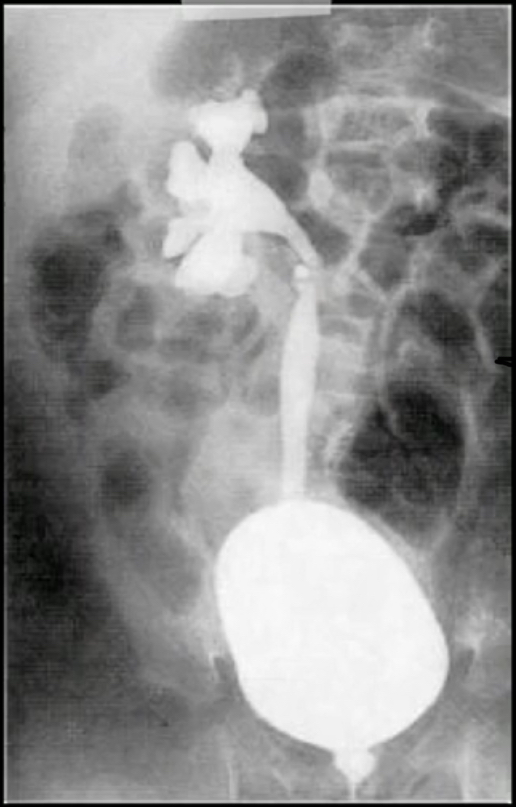

Que exame é este e o que ele revela?

É uma uretrocistografia miccional

Ela está revelando um refluxovesicoureteral unilateral à direita